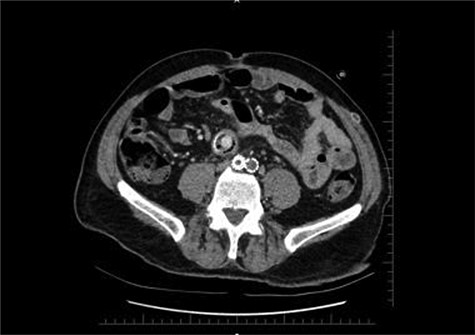

Coronal CT section shows straight part of the Dacron graft in the jejenum.

During the first days of December 2018, the patient visited another medical center because of fatigue, difficulty in breathing, lower back pain and inability to walk. His blood biochemistry revealed a very high CRP level (350 mg/dl), and complete blood count revealed a very high level of white blood cells (21 000/ul). An abdominal CT scan illustrated part of the graft was totally eroded into the small intestine (Figs 1–3). The patient was referred to my office and an infectious disease specialist. He had high body temperature (39.5°C) and was lying on the bed with lower extremities adducted to the chest. Antibiotic and supportive treatment was started. Emergency surgery was performed. We found an 8–10 cm of the straight part of the graft had become totally incorporated into the proximal part of the jejenum. The graft was freed, and 10–15 cm of the jejenum was resected and anastomosed. The area was irrigated with saline and hypochlorous acid. We then put a 20 x 10 composite mesh between the vascular graft and the intestine using a non-adhensive surface facing the intestine to prevent future graft and intestine interactions and erosion. After hemostasis, two drains were placed retroperitonally, and the abdomen was closed. On the fourth post-operative day, a high body temperature and high CRP levels were recorded. An abdominal CT revealed retroperitoneal abcess formation. During relaparotomy, the anastomosis was found to be intact, and the retroperitoneal abscess was drained and irrigated with saline. The drains were reinserted. After a month, he once again started to have high fever and high CRP levels. Again, an abdominal CT revealed abscess formation. This time, the abscess was approached transcutaneously. By making an incision in the proximal left lomber region, the abscess was drained. Another incision was made distally, and two drains were placed in the retroperitoneal area.